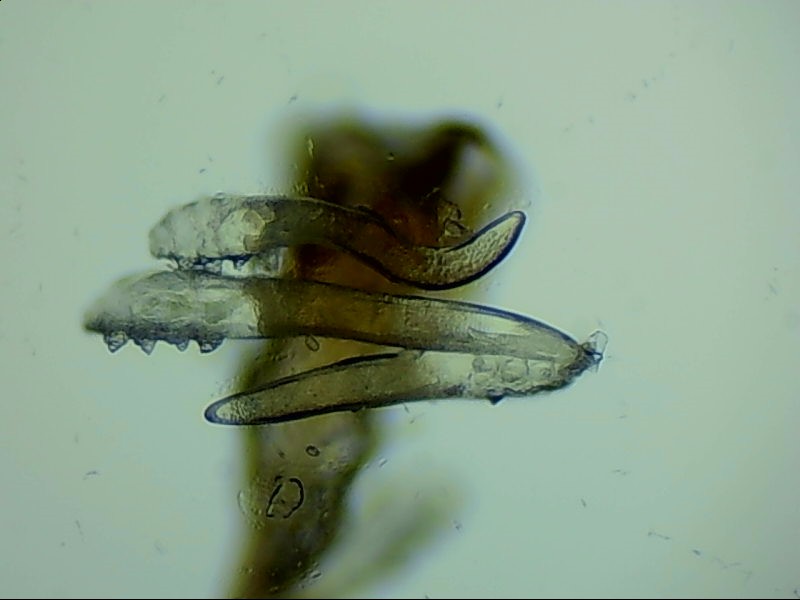

蠕形螨是螨蟲的一種,主要寄居在毛囊中。蠕形螨以分泌的油脂、分泌物為食,所以眼部寄居著蠕形螨的患者多有亂睫或睫毛脫落的癥狀。

蠕形螨寄居后,它們以睫毛毛囊里面的油脂為食。隨著油脂的缺失,睫毛會(huì)長的東倒西歪,如果毛囊里的油脂都被吃光了,就會(huì)出現(xiàn)睫毛脫落這種蠕形螨性瞼緣炎的典型癥狀。

身體健康時(shí),蠕形螨就吃吃油脂,夜里爬出來活動(dòng)、交配,與我們相安無事,一旦身體的免疫力下降,蠕形螨的活動(dòng)、產(chǎn)的卵、排泄的廢物和分泌的分泌物都會(huì)引起過敏反應(yīng)。患者會(huì)出現(xiàn)眼癢、異物感、眼干、瞼緣充血、鱗屑、睫毛根部袖套狀分泌物及睫毛脫落等癥狀,嚴(yán)重者可并發(fā)結(jié)膜及角膜病變,給生活帶來不便和困擾。